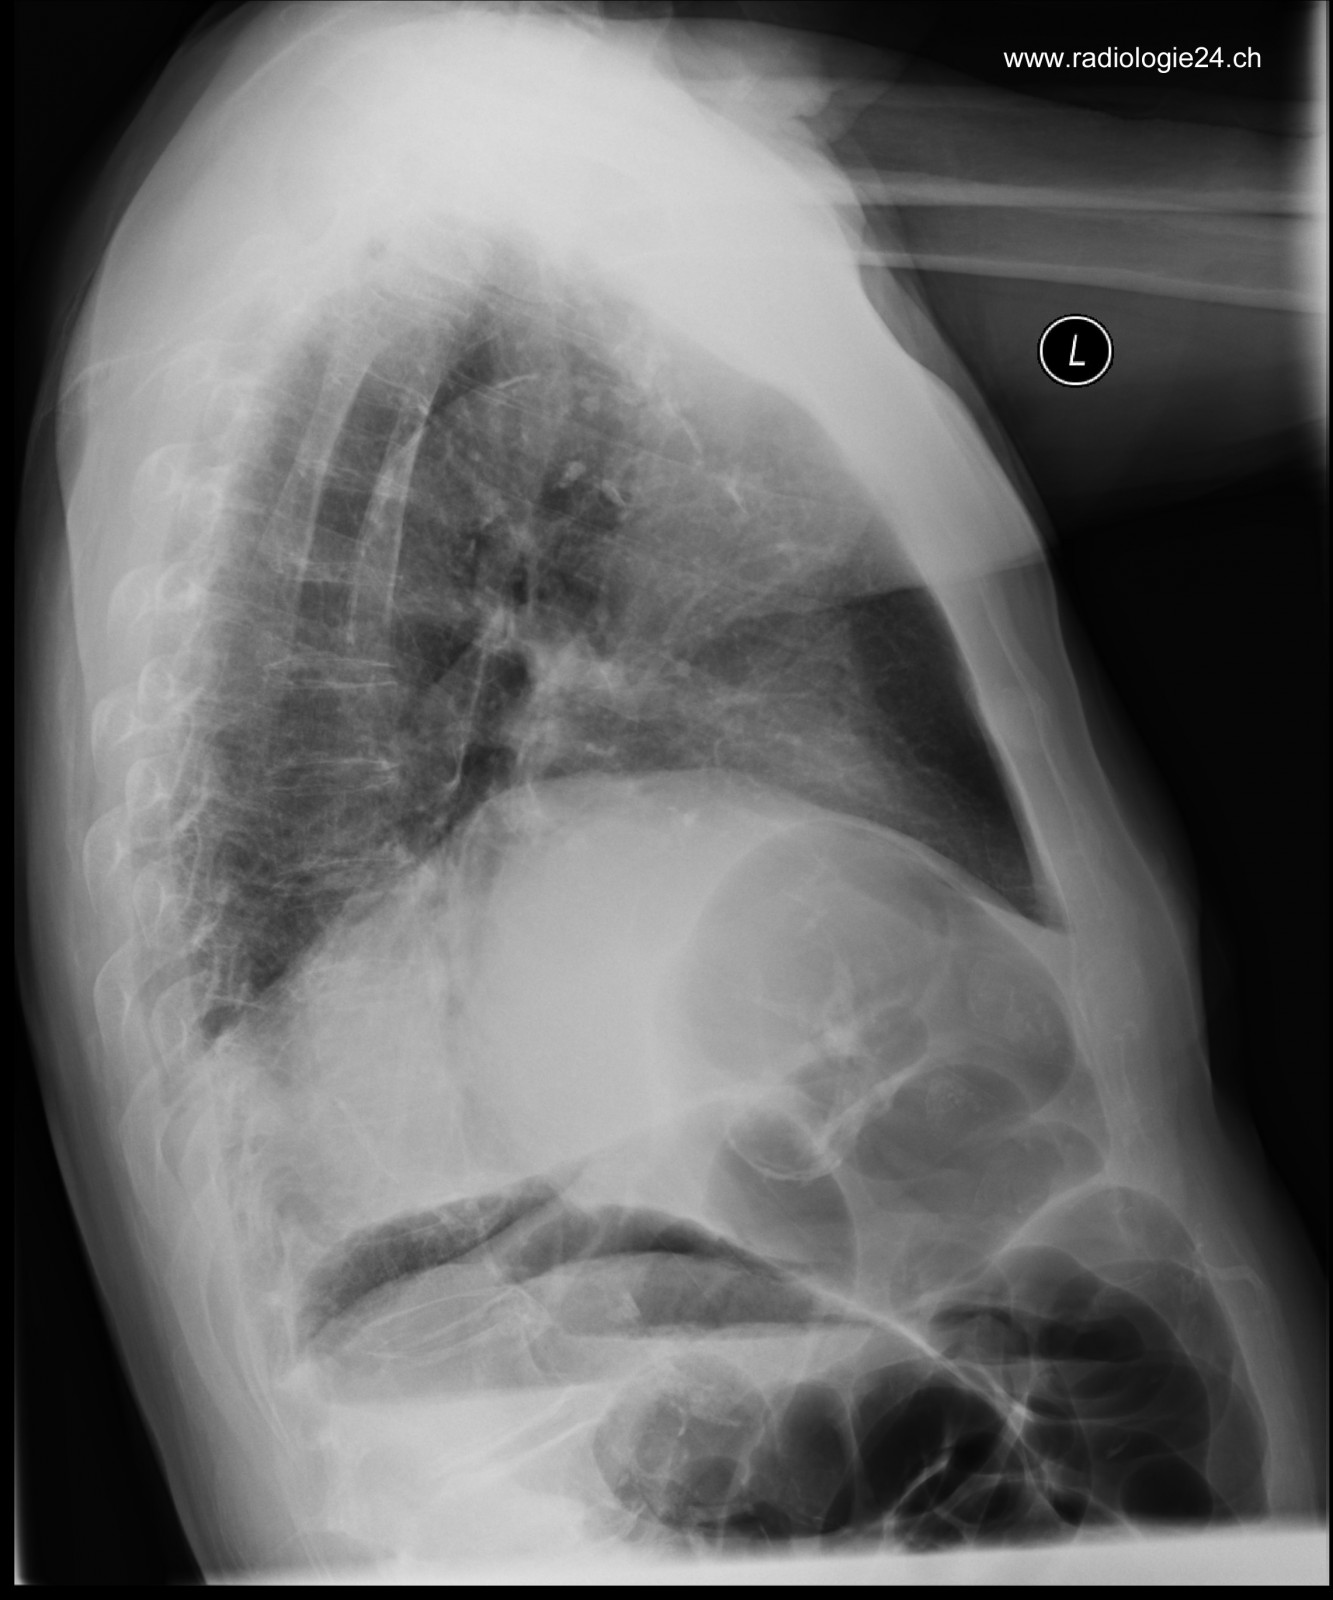

Röntgenfall des Monats Juli 2017 mit Auflösung

78 jähriger Patient mit zunehmender Dyspnoe und Thoraxschmerzen